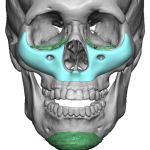

People considering custom jawline implants tend to ask a consistent set of questions. These generally fall into four categories: outcomes, safety, process, and recovery. What are custom jawline implants? Custom jawline implants are patient-specific implants designed from a 3D CT scan of your face. Unlike standard implants, they are digitally created to match your exact Read More…